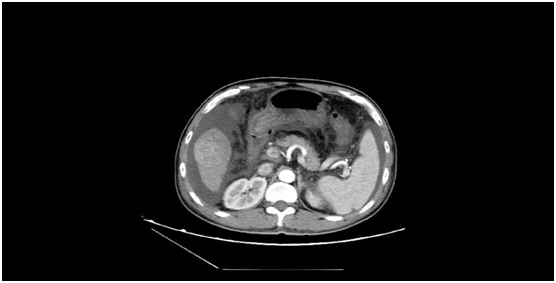

術(shù)前發(fā)現(xiàn)患者的肝臟5段有一個5.5cm大小的惡性腫瘤,此外還有大量腹水、門脈高壓癥、脾功能亢進(jìn),同時合并有消化道出血、肝功能差等癥狀。而在患者的肝臟7段,亦存在一個2cm大小的肝內(nèi)轉(zhuǎn)移灶。

術(shù)后復(fù)查CT見腫瘤全部失去了活性